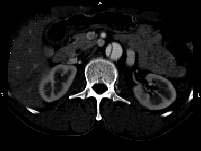

问题 请看一组主动脉的CT增强图像,正确的描述和结论是 ( )

选项 A、真腔较假腔小 B、真假腔之间线状低密度影为内膜片影 C、主动脉瘤 D、主动脉夹层 E、主动脉血栓 一、多项选择题

答案 ABD